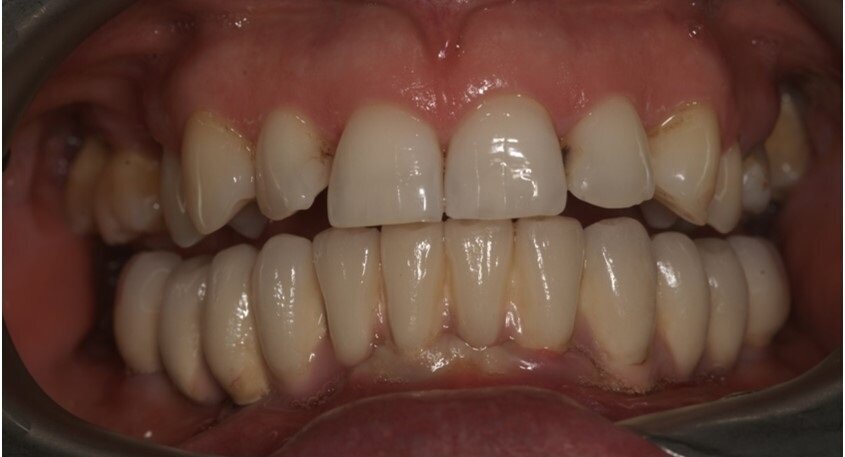

Badaniem wewnątrzustnym stwierdzono kieszenie o głębokości ponad 4 mm, wydzielinę ropną i krwawą, wskaźniki higieny wynosiły odpowiednio: API 25%, SBI 20%, wszystkie zęby w żuchwie wykazywały 3. stopień rozchwiania (Ryc. 1).

Wykonanie badania tomograficznego potwierdziło diagnozę o zaawansowanej nierokującej chorobie przyzębia (Ryc. 2). Po konsultacji została podjęta decyzja o ekstrakcji wszystkich zębów w żuchwie, natychmiastowym wprowadzeniu implantów z jednoczesną czasową odbudową protetyczna stałą mocowaną na wszczepionych implantach. Zlecono rutynowe badanie lekarskie i laboratoryjne.